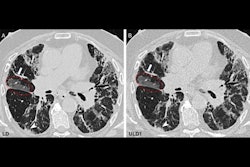

Wradzidlo and colleagues compared image quality and radiation dose between a dual-energy CT (DECT) device and a photon-counting CT scanner. Their study included 70 patients who underwent abdominal, contrast-enhanced CT between November 2021 and February 2022. The patients had both a DECT exam and a follow-up exam with a photon-counting device (median time between the two scans was four months). The researchers assessed radiation dose between the two types of studies using the following metrics: CT dose index, dose length product, and size-specific dose estimation. Two radiologists scored the images for quality, particularly lesion visibility.

The group found that photon-counting CT reduced the size-specific dose estimation by 32%, without degrading image quality.

Additionally, the two readers rated lesion conspicuity higher on the photon-counting CT exams compared with the DECT exams, especially in the third quartile, the team noted.

"[Photon-counting CT] enables oncologic abdominal CT with a significantly reduced dose while retaining image quality similar to ... DECT," they concluded.